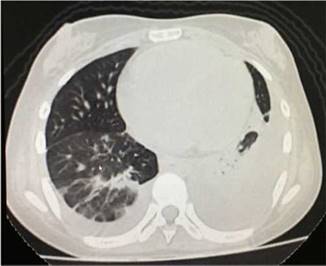

The simple chest X-ray showed the presence of pleural effusions and an image suggestive of left basal consolidation, despite the fact that the patient did not have cough, sputum or fever (Fig. 1). Left pleural effusion with ipsilateral compressive atelectasis and parenchymal bands in the right base were evidenced in the simple chest CT scan (Fig. 2). The echocardiogram reported a preserved ejection fraction with an elevated pulmonary artery systolic pressure of 42 mm Hg (Vr. PASP lower than 36 mm Hg). The Systemic Disease Activity Index (SLEDAI) was calculated in 21 points, considering it a severe exacerbation of the SLE. Treatment was started with prednisolone at 30 mg/day, with which the patient presented improvement of the dyspnea and of the oxygen saturation.

Fig. 2 Simple chest tomography with evidence of left pleural effusion associated with ipsilateral compressive atelectasis and parenchymal bands in the right base.